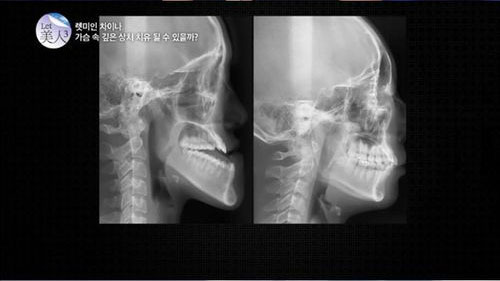

日前播出的Story on《Let美人》节目中,播出了该节目首次制作的《Let美人中国篇》。节目在众多报名者中选中了一名“兜齿少女”郭芳媛(音)——因为下颌出奇地长从小就被戏称为“外星人”。她虽然只有18岁,但自从3岁时从椅子上跌落后,上颚几乎不再生长,下颚却越长越长,成了如今“地包天”的样子。除相貌外,因牙齿咬合不齐,她咀嚼食物也很吃力。

经过60天的手术,郭芳媛的外貌完全改变,被节目称为“有了让人既羡慕又惊讶的芭比娃娃一样的脸”。郭芳媛父母对节目相关人士说:“我们都认不出女儿了,她的下巴好看多了。现在想来,把女儿送到韩国是个明智的决定。”